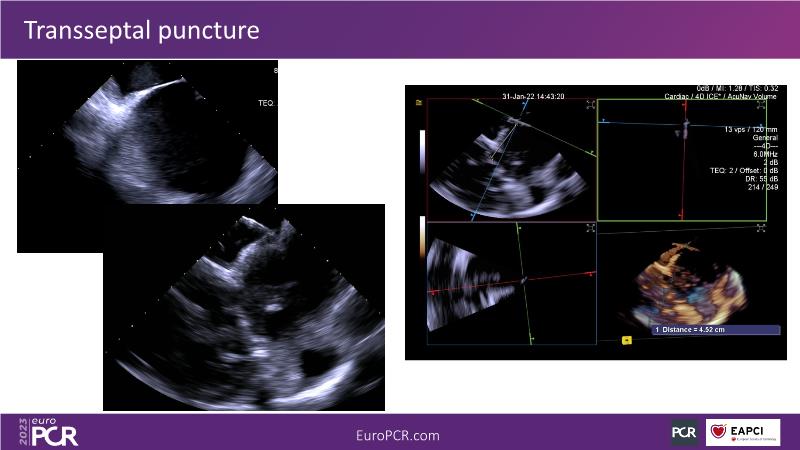

Use of 4D ICE in tricuspid and mitral valve interventions

Watch this session to know the challenges of TV imaging, to get an overview on 4D ICE technology, and to study both a transcatheter tricuspid valve procedure and a transcatheter mitral valve procedure through different case presentations, that will then be discussed.

- To get familiar with the 4D ICE technology and how it can support the imaging and guidance in complex structural heart disease interventions

- To understand the use of 4D ICE and benefits in tricuspid and mitral valve interventions